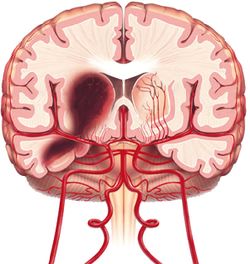

النزف الدماغي «تمزق شريان صغير داخل الدماغ يؤدي إلى خروج الدم من الوعاء إلى النسيج الدماغي».

1ـ النزيف الدماغي (أو داخل الدماغ) intracerebral hemorrhage: يؤلف نحو 10% من الأمراض الوعائية الدماغية. وفيه يحدث نزيف داخل النسيج الدماغي، مما قد يسبب خطورة كبيرة على الحياة نتيجة انضغاط المراكز الحيوية في الدماغ (كتلك المسؤولة عن التنفس).

ـ عوامل الخطورة: أهم أسباب النزيف الدماغي هو ارتفاع الضغط الشرياني. ومن الأسباب الأخرى ضعف الأوعية الدماغية لدى الكهول، كما قد يسبب استعمال المميعات الدموية ازدياد احتمال الوفاة في حال حدوث نزيف دماغي.